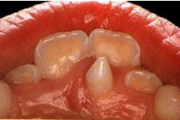

Normaalse jäävhammaskonna pilt küljelt ja eest vaadatuna.